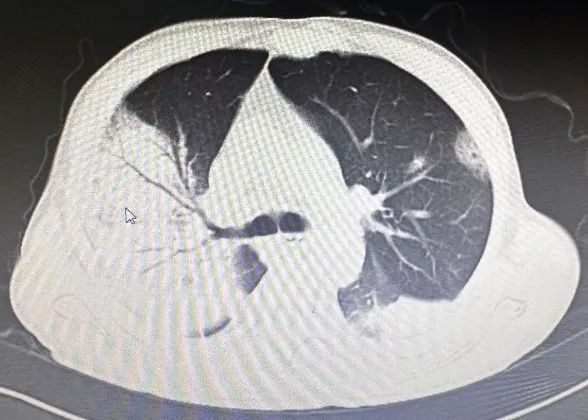

经积极抗感染治疗,患者仍持续处于稽留热,体温最高达39.8℃,并逐渐出现胸闷、气短症状伴有咳嗽、咳痰。右肺中下叶可闻及少量散在湿啰音及胸膜摩擦音。感染指标持续上升,复查肺部CT提示:双肺多发感染性病变,较前进展。

调整治疗后,患者病情仍未见好转并逐步恶化,遂转入ICU继续治疗。在我院ICU予以无创呼吸机通气,为了明确病因,行支气管镜检查取样成功,结果显示:鹦鹉热衣原体。结合血常规、CRP和胸部CT检查以及他饲养鸟类动物病史,此时就明确了,原来患者这次是鹦鹉热衣原体引起的肺部感染——俗称“鹦鹉热”。

重症鹦鹉热患者可于短期内出现呼吸衰竭和ARDS等呼吸系统症状。胸部CT检查以炎性病变始于单侧肺下叶多见,加重后累及双侧肺叶,上下肺均可受累,可合并有小片状的磨玻璃影、结节影、实变影和小叶间隔增厚,以胸膜下分布为主,常见“支气管充气征”、“细网格征”,可见“晕征”,常伴有胸腔积液,可伴有肺门及纵隔淋巴结肿大。治疗上常用的Cps抗菌药物包括四环素类、新型四环素类衍生物、大环内酯类和氟喹诺酮类等药物。